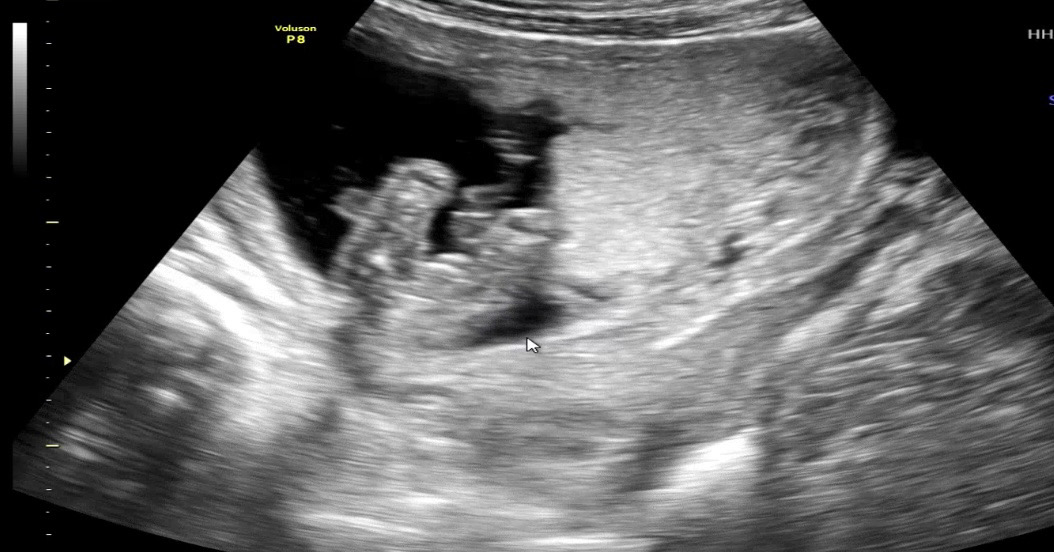

다리사이 매끈해보이는데ㅠㅜ아닌가용?ㅠㅜ

15주 성별 확인했어요 둘째

첫째가 아들이라 둘째 아가는 딸이길 남편이랑 저랑 둘이 간절히 바랬는데 ㅋㅋ 남자 형제 축하드린다고 하시네요 😂 아무리봐도 딸같은데… ㅠㅠㅠㅠㅠ 성별반전 없겠죠 ㅋㅋ 어떻게 보이시나요

저도 그래서 딸이라 생각했는데 ㅠㅠㅠ 훌쩍 다른 각도에선 또 보이셨나봐요… ㅠㅠ 힝